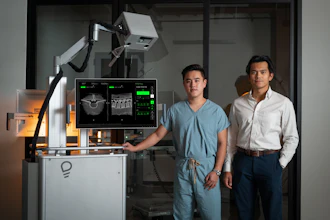

GE HealthCare today announced a collaboration with NVIDIA, expanding the existing relationship between the two companies to focus on autonomous imaging, beginning with autonomous X-ray technologies and autonomous applications within ultrasound.

GE HealthCare aims to develop AI-enabled X-ray and ultrasound systems by using the new NVIDIA Isaac for Healthcare platform, built on NVIDIA’s three computers used to build physical AI, including NVIDIA Omniverse for robotic simulation workflows. Using the NVIDIA Cosmos platform for synthetic data generation, physics-based sensor simulation, imitation, and reinforcement learning, GE HealthCare plans to train, test, and tune autonomous ultrasound and X-ray devices in a virtual environment before deployment in the physical world.

NVIDIA and GE HealthCare will initially focus on autonomous development within X-ray systems, specifically the potential utilization of the NVIDIA Isaac for Healthcare and Jetson platforms. GE HealthCare plans to explore Isaac for Healthcare platform and synthetic data generation to simulate various scenarios. This will help to automate repetitive tasks performed by a technologist in the patient exam room. The goal is to enable care teams to focus more of their time on direct patient care and complex cases. The companies will also explore the development of machine-to-patient interactions to autonomously lead the patient through the scan journey.